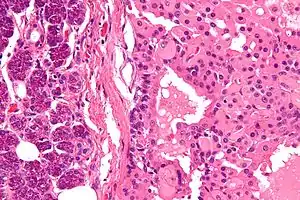

| Micrograph of a parotid gland oncocytoma (right of image). Normal parotid gland is also present (left of image). H&E stain. | |

The salivary gland oncocytoma is a well-circumscribed, benign neoplastic growth also called an oxyphilic adenoma. It comprises about 1% of all salivary gland tumors. The histopathology is marked by sheets of large swollen polyhedral epithelial oncocytes, which are granular acidophilic parotid cells with centrally located nuclei. The granules are created by the mitochondria.